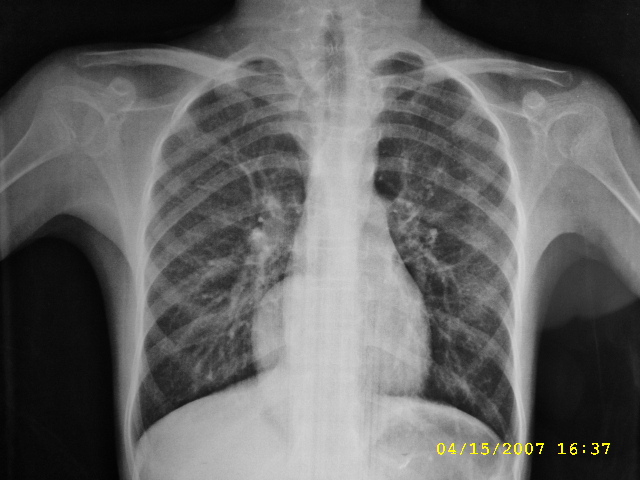

标题: PED0109:女,12,后纵隔占位十余年

女,12,后纵隔占位十余年。